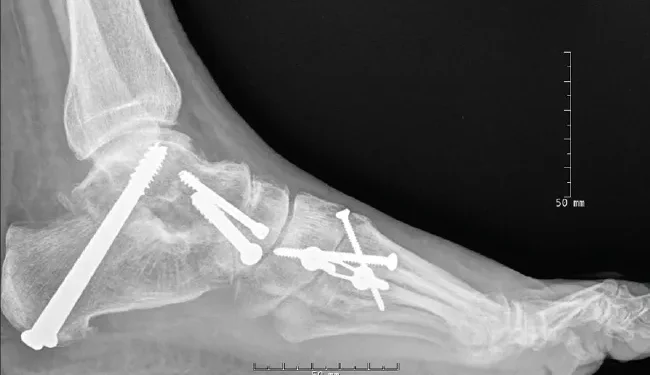

Foot and ankle conditions like arthritis or injuries can be painful and limit movement. While treatments like therapy or medication help, sometimes surgery, like hindfoot fusion, is needed. This procedure fuses bones in the heel and ankle to enhance stability and reduce pain. It has benefits and risks like any surgery.

One of the main benefits of hindfoot fusion is that it can significantly reduce pain and discomfort. By fusing bones in the heel and ankle, this procedure eliminates any movement between them, which is a common source of pain for people with foot and ankle conditions.

Hindfoot fusion also improves stability by creating a solid connection between the bones in the heel and ankle. This can help with walking, running, and other activities that require weight-bearing on the foot.

In some cases, hindfoot fusion can also correct structural issues in the foot and ankle. For example, if a person has malalignment or deformities in their feet due to conditions like flat feet or high arches, this surgery can help correct them and improve overall foot and ankle function.